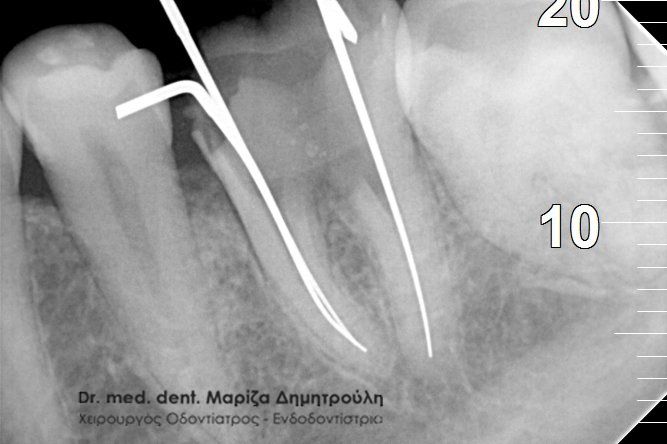

Στο συγκεκριμένο περιστατικό είχε πραγματοποιηθεί από συνάδελφο απονεύρωση δοντιού και ο ασθενής αναφέρει τις έντονες ενοχλήσεις που του προκαλεί το δόντι το τελευταίο τρίμηνο. Η ακτινογραφία αποκάλυψε αφενός το μικρό μήκος της απονεύρωσης στην εγγύς ρίζα του δοντιού και αφετέρου την ύπαρξη περιακρορριζικής αλλοίωσης στην άπω ρίζα δοντιού, η οποία έχει τη μορφή μιας μαύρης σαφώς περιγεγραμμένης σκιάς. Η εμφάνιση της αλλοίωσης αυτής σημαίνει οτι το δόντι έχει φλεγμονή, η οποία πρέπει να αντιμετωπιστεί.

ΠΡΙΝ ΜΕΤΑ

Στον παραπάνω ασθενή έγινε επανάληψη απονεύρωσης και εντοπίστηκε και τέταρτος ριζικός σωλήνας, ο οποίος δεν είχε βρεθεί στην πρώτη ενδοδοντική θεραπεία.

Η ασθενής παραπονιόταν για συνεχή πόνο στο συγκεκριμένο δόντι, το οποίο είχε απονευρωθεί πριν χρόνια. Μετά από τη λήψη ακτινογραφίας διαπιστώθηκε οτι στην πρώτη ενδοδοντική θεραπεία δε είχε μετρηθεί σωστά το μήκος της ρίζας του δοντιού. Μετά την επανάληψη της απονεύρωσης το δόντι καθαρίστηκε και εμφράχθηκε σε όλος το μήκος της ρίζας, όπως δείχνει και η δεξιά αντινογραφία.